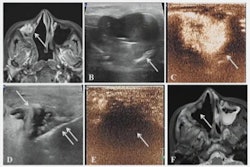

EVT is a minimally invasive image-guided surgical procedure used to dissolve blood clots in stroke patients, and thus restore blood flow (reperfusion) to prevent further brain damage. Recent clinical trials have provided robust evidence that the procedure improves functional outcomes among patients with large vessel occlusion (LVO), the authors wrote.

To address this knowledge gap, the group compared safety and efficacy outcomes in 126 patients older than 80 and 282 patients ages 80 and younger. Patients received EVT for acute ischemic stroke with large infarct at one of 25 German stroke centers between May 2015 and December 2021. Primary outcomes of the study were independent ambulation and mortality rates after 90 days.